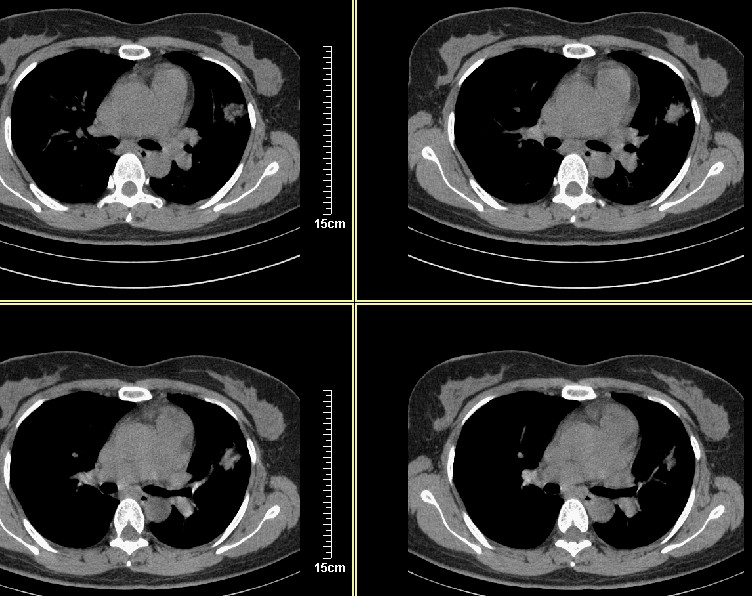

标题: CT8248B:女45岁,三天后复查,经支气管镜注药,会不会是肺 [打印本页]

标题: CT8248B:女45岁,三天后复查,经支气管镜注药,会不会是肺

应该能确定是恶性病变,三天前周围出现的淡薄景应该是肺泡内积血

3天后复查:病变明显好转、吸收:考虑炎症可能性大

支气管注药后3天后复查:病变明显好转、吸收:考虑炎症可能性大.

3天后复查:病变明显好转、吸收:考虑炎症可能性大.肿瘤待排

病灶似乎呈片样,密度不均匀,3天后复查:病变明显好转、吸收:考虑炎症可能性大 。

气管注药后3天后复查:病变明显好转、吸收:考虑炎症可能性大,肺癌待排!